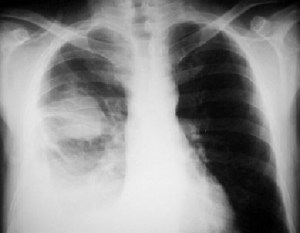

Signo que describe al derrame pleural atrapado en la cisura menor, especialmente en pacientes con insuficiencia cardiaca. El derrame loculado en la proyección posteroanterior se ve como una lesión nodular o masa que simula un tumor sólido (imagen superior). Sin embargo, la evolución rápida hacia la desaparición de esta lesión sugiere que se trata de derrame.

Vemos en las imágenes un tumor fantasma que desaparece en el control realizado cinco días más tarde.

En la primera imagen, la presencia de derrame pleural asociado y el engrosamiento del resto de la cisura menor, visible como una línea superpuesta al tumor fantasma, sugieren el diagnóstico.